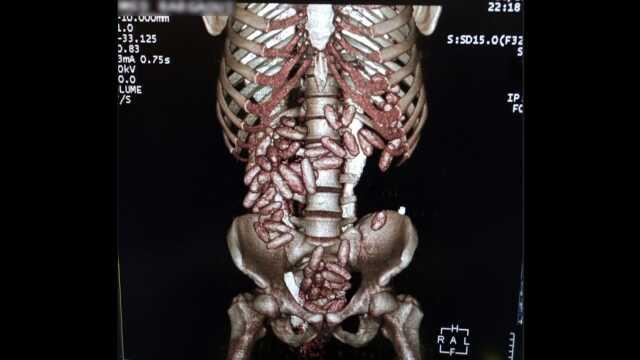

Uçağın iniş yapmasının ardından muhafaza ekiplerince yolcunun fiziki takibine başlandı. Gümrük kontrol noktasında durdurulan şüphelinin x-ray taramasından geçirilen valizinde herhangi bir suç unsuruna rastlanılmadı. Ekiplerin üst araması yaptığı esnada şüphelinin karın bölgesinde şişkinlik olduğu fark edildi. Bunun üzerine tomografi cihazına alınan şüphelinin çok sayıda kapsül yuttuğu tespit edildi.

Sağlık kuruluşunda yapılan muayene sonucunda çıkarılan kapsüllerin içerisindeki maddenin kokain olduğu belirlenirken, kuryenin 820 gram kokain yuttuğu ortaya çıktı. Gaziosmanpaşa Cumhuriyet Başsavcılığı'nın başlattığı soruşturma kapsamında şüpheli tutuklandı.